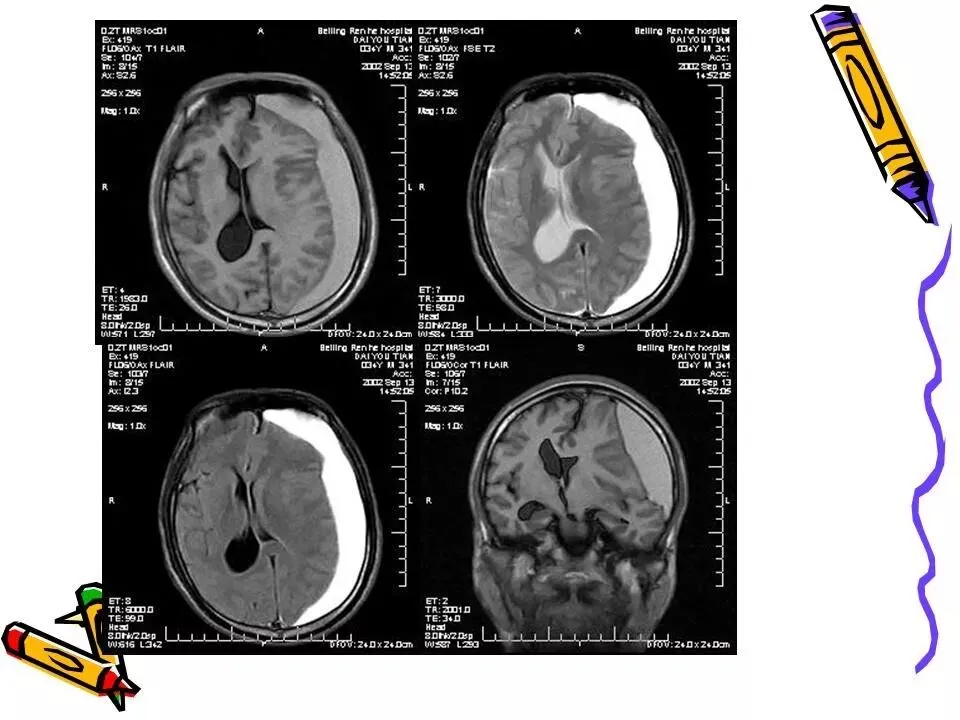

>常见颅脑外伤CT诊断(PPT)

常见颅脑外伤CT诊断(PPT)